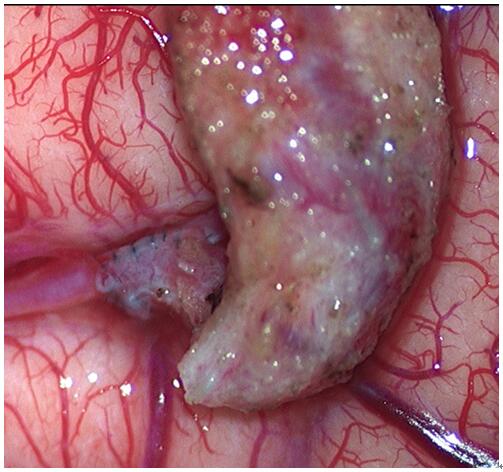

高倍显微镜下的血管吻合口,直径只有1mm不到,需要用10-0缝线吻合12-14针。